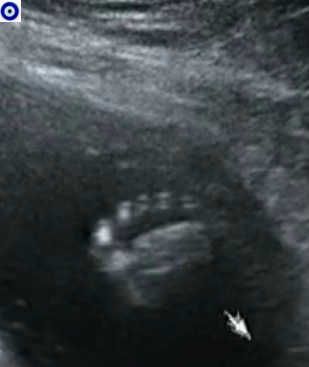

Фото с 2го скрининга)

Результаты: УЗИ, КТГ, доплера, скринингаБыли на УЗИ в 20.2 недель, все у нас хорошо, тонуса и низкой плацентации уже нет, плацента от зева уже на 6.5 см)

Ростом мы 25 см, весим 300 грамм :)